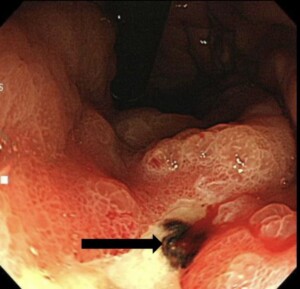

*NSAIDs潰瘍 出血していたため、緊急内視鏡検査を行い止血術を行いました。

https://www.tamapla-ichounaika.com/knowledge/category/post-24885/